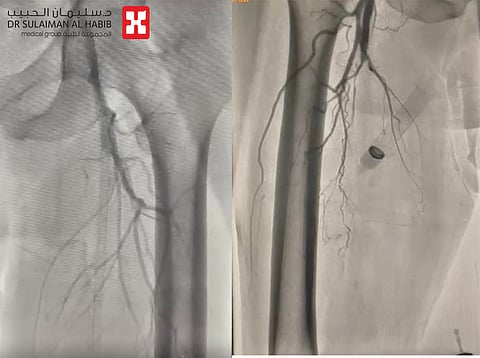

وأضاف أن المريض تمت معاينته من قِبَل أطباء الجراحة العامة والعظام والأوعية الدموية، وبعد الاطلاع على صور الأشعة المقطعية، تم تقييم حالته وتصنيفه كحالة جراحية إسعافية؛ إلا أن تعقيدات الحالة العامة للمريض جعلت من التدخل الجراحي والتخدير أمرًا ينطوي على الكثير من المخاطر التي قد تُهدد حياته، فتم تحويل المريض إلى عيادة القلب لبحث إمكانية استعادة التروية الدموية عبر القسطرة؛ حيث تمت إعادة تقييم لحالته من قِبَل الفريق الطبي ومراجعة كل التحاليل المخبرية والأشعة المقطعية، التي بيّنت وجود انقطاع للتروية الدموية بعد تفرع الأبهر البطني، في الجهتين اليمنى واليسرى بشكل شبه تام مع عدم وجود جريان دموي، وعدم وضوح الأوعية الدموية؛ فتم وضع خطة لإجراء قسطرة وعائية عاجلة لفتح الشرايين؛ لتجنب بتر الأطراف السفلية، ومضاعفات أخرى خطيرة، خاصة وأن التحاليل أظهرت أيضًا ارتفاعًا حادًا في مشعرات الالتهاب، نتيجة حدوث التهاب في العظم على مستوى القدم وتضررًا لوظائف الكلى.

واستطرد الدكتور الحجيلي: خضع المريض لعمليتين استمرتا مجتمعتيْن نحو 6 ساعات، جرى فيها إزالة كل الانسدادات وزراعة 6 دعامات، وقد تكللت جهود الفريق الطبي -ولله الحمد- باستعادة الجريان الدموي كاملًا على مستوى الطرفين السفليين وفتح كل الانسدادات، ومن ثم تم تحويل المريض إلى قسم العناية القلبية لإتمام المراقبة والعلاج، قبل تحويله لاحقًا لقسم العظام لمتابعة علاج التهاب العظم والتقرحات.